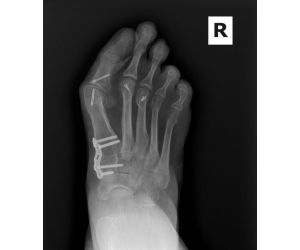

Correcting MIS Lapidus

Dr. Kris Di Nucci

MIS surgeons — here is a patient who presents 10 months after an MIS Lapidus arthrodesis. She reports recurrence of her bunion and mild sesamoid...